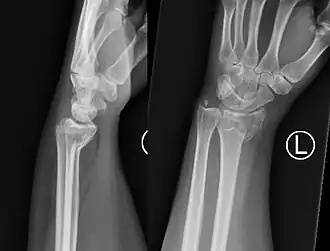

Fractura de Smith muñeca izquierda

La fractura de Goyrand-Smith o fractura de Smith (o fractura de Colles invertida) es una fractura del extremo distal del radio con desplazamiento palmar del fragmento y la mano, respecto del radio; esto produce la deformidad en pala de jardinería. Su epónimo se debe al médico, cirujano y político francés Gaspard Goyrand[1]​ y al cirujano ortopédico irlandés Robert William Smith que la describe en su obra Treatise on Fractures in the Vicinity of Joints, and on certain forms of Accidents and Congenital Dislocations, publicada en 1847.[2]

El fragmento de fractura distal se desplaza de forma volar (ventralmente), a diferencia de la fractura de Colles, que el fragmento se desplaza dorsalmente. Dependiendo de la gravedad del impacto, puede haber uno o varios fragmentos y puede o no afectar la superficie articular de la articulación de la muñeca.

El diagnóstico inicial es clínico mediante al exploración, haciendonos sospechar la presencia de este tipo de fractura si se presentan los signos detallados arriba. Ante esta sospecha, el diagnóstico final apropiado de este tipo de fracturas necesita la realización de una radiografía simple del antebrazo distal y del carpo en al menos dos proyecciones: antero-posterior y lateral. En algunos casos, una vez realizada la radiografía simple, cuando las imágenes muestren que se trata de una fractura multifragmentario o compleja, la realización de una tomografía computarizada simple de la lesión puede ser útil para guiar el tratamiento.